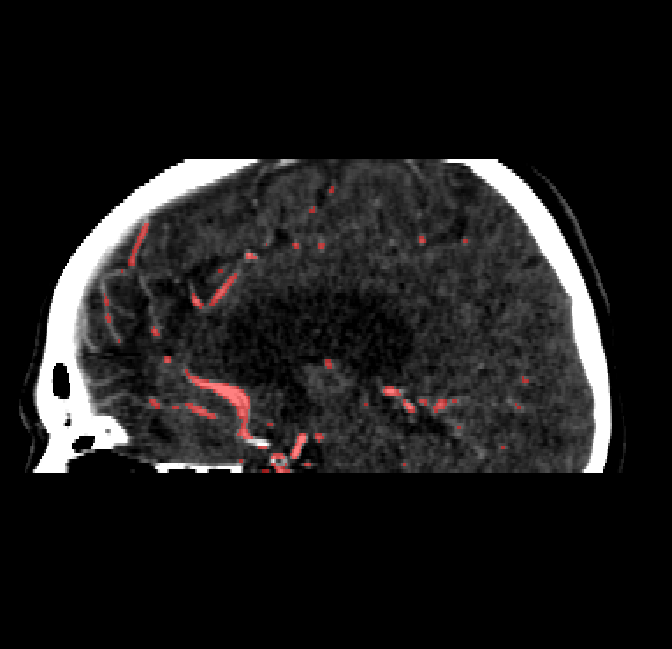

After fine-tuning, the two pre-train conditions appear to have little or no difference in terms of qualitative performance at the vessel segmentation task. However, when compared to the models trained only on real data, there are noticeable differences. Throughout Figures 4.3-4.9, the model pre-trained on scans with original CT noise is to be taken as representative of segmentation performed by the Perlin noise pre-training condition. Images showing the hand-labeled ground truth, as well as the unlabeled slice, are presented for comparison.

Figure 4.8: Side view of segmentations on regions near the left side of the skull. Unaltered image (left). No pretrain model (mid-left). Fine-tuned model (mid-right). Hand-labeled ground truth (right).

Refer to caption

Figure 4.9: Side view of segmentations. Unaltered image (left). No pretrain model (mid-left). Fine-tuned model (mid-right). Hand-labeled ground truth (right).

The models appear to have a hard time segmenting vessels close to the skull surface. The model trained exclusively on patient data appears to struggle far more for these types on conditions than the fine-tuned models. Figure 4.8 shows an example of the fine-tuneds model having close to no trouble segmenting vessels near the left side of the skull, while the baseline model suffers heavily from false negatives. To lesser degree, this effect can also be observed in the frontal lobe of Figure 4.9 In the other hand, Figure 4.7 presents an example of both models failing to segment vessels near the top of the skull.

In the other hand, it should be noted that fine-tuned models suffered from false positives more often than models with no pre-training. The fine-tuned models appeared to occasionally segment regions near the skull, which although similar in intensity to vessels, had no resemblance in terms of shape. Examples of this are seen in Figure 4.4 near the occipital bone and near the right temporal bone. Examples of oversegmentation were observed to happen commonly around the internal carotid arteries. This is likely due to the amount of contact surface between the artery and the surrounding bone. There was also a tendency for all model conditions to segment bone regions that were similar in shape to large vessels (Figures 4.3 and 4.4). Bone structures in such regions have similar pixel intensities to the arteries transporting contrast material, which could explain the source of confusion for a model.